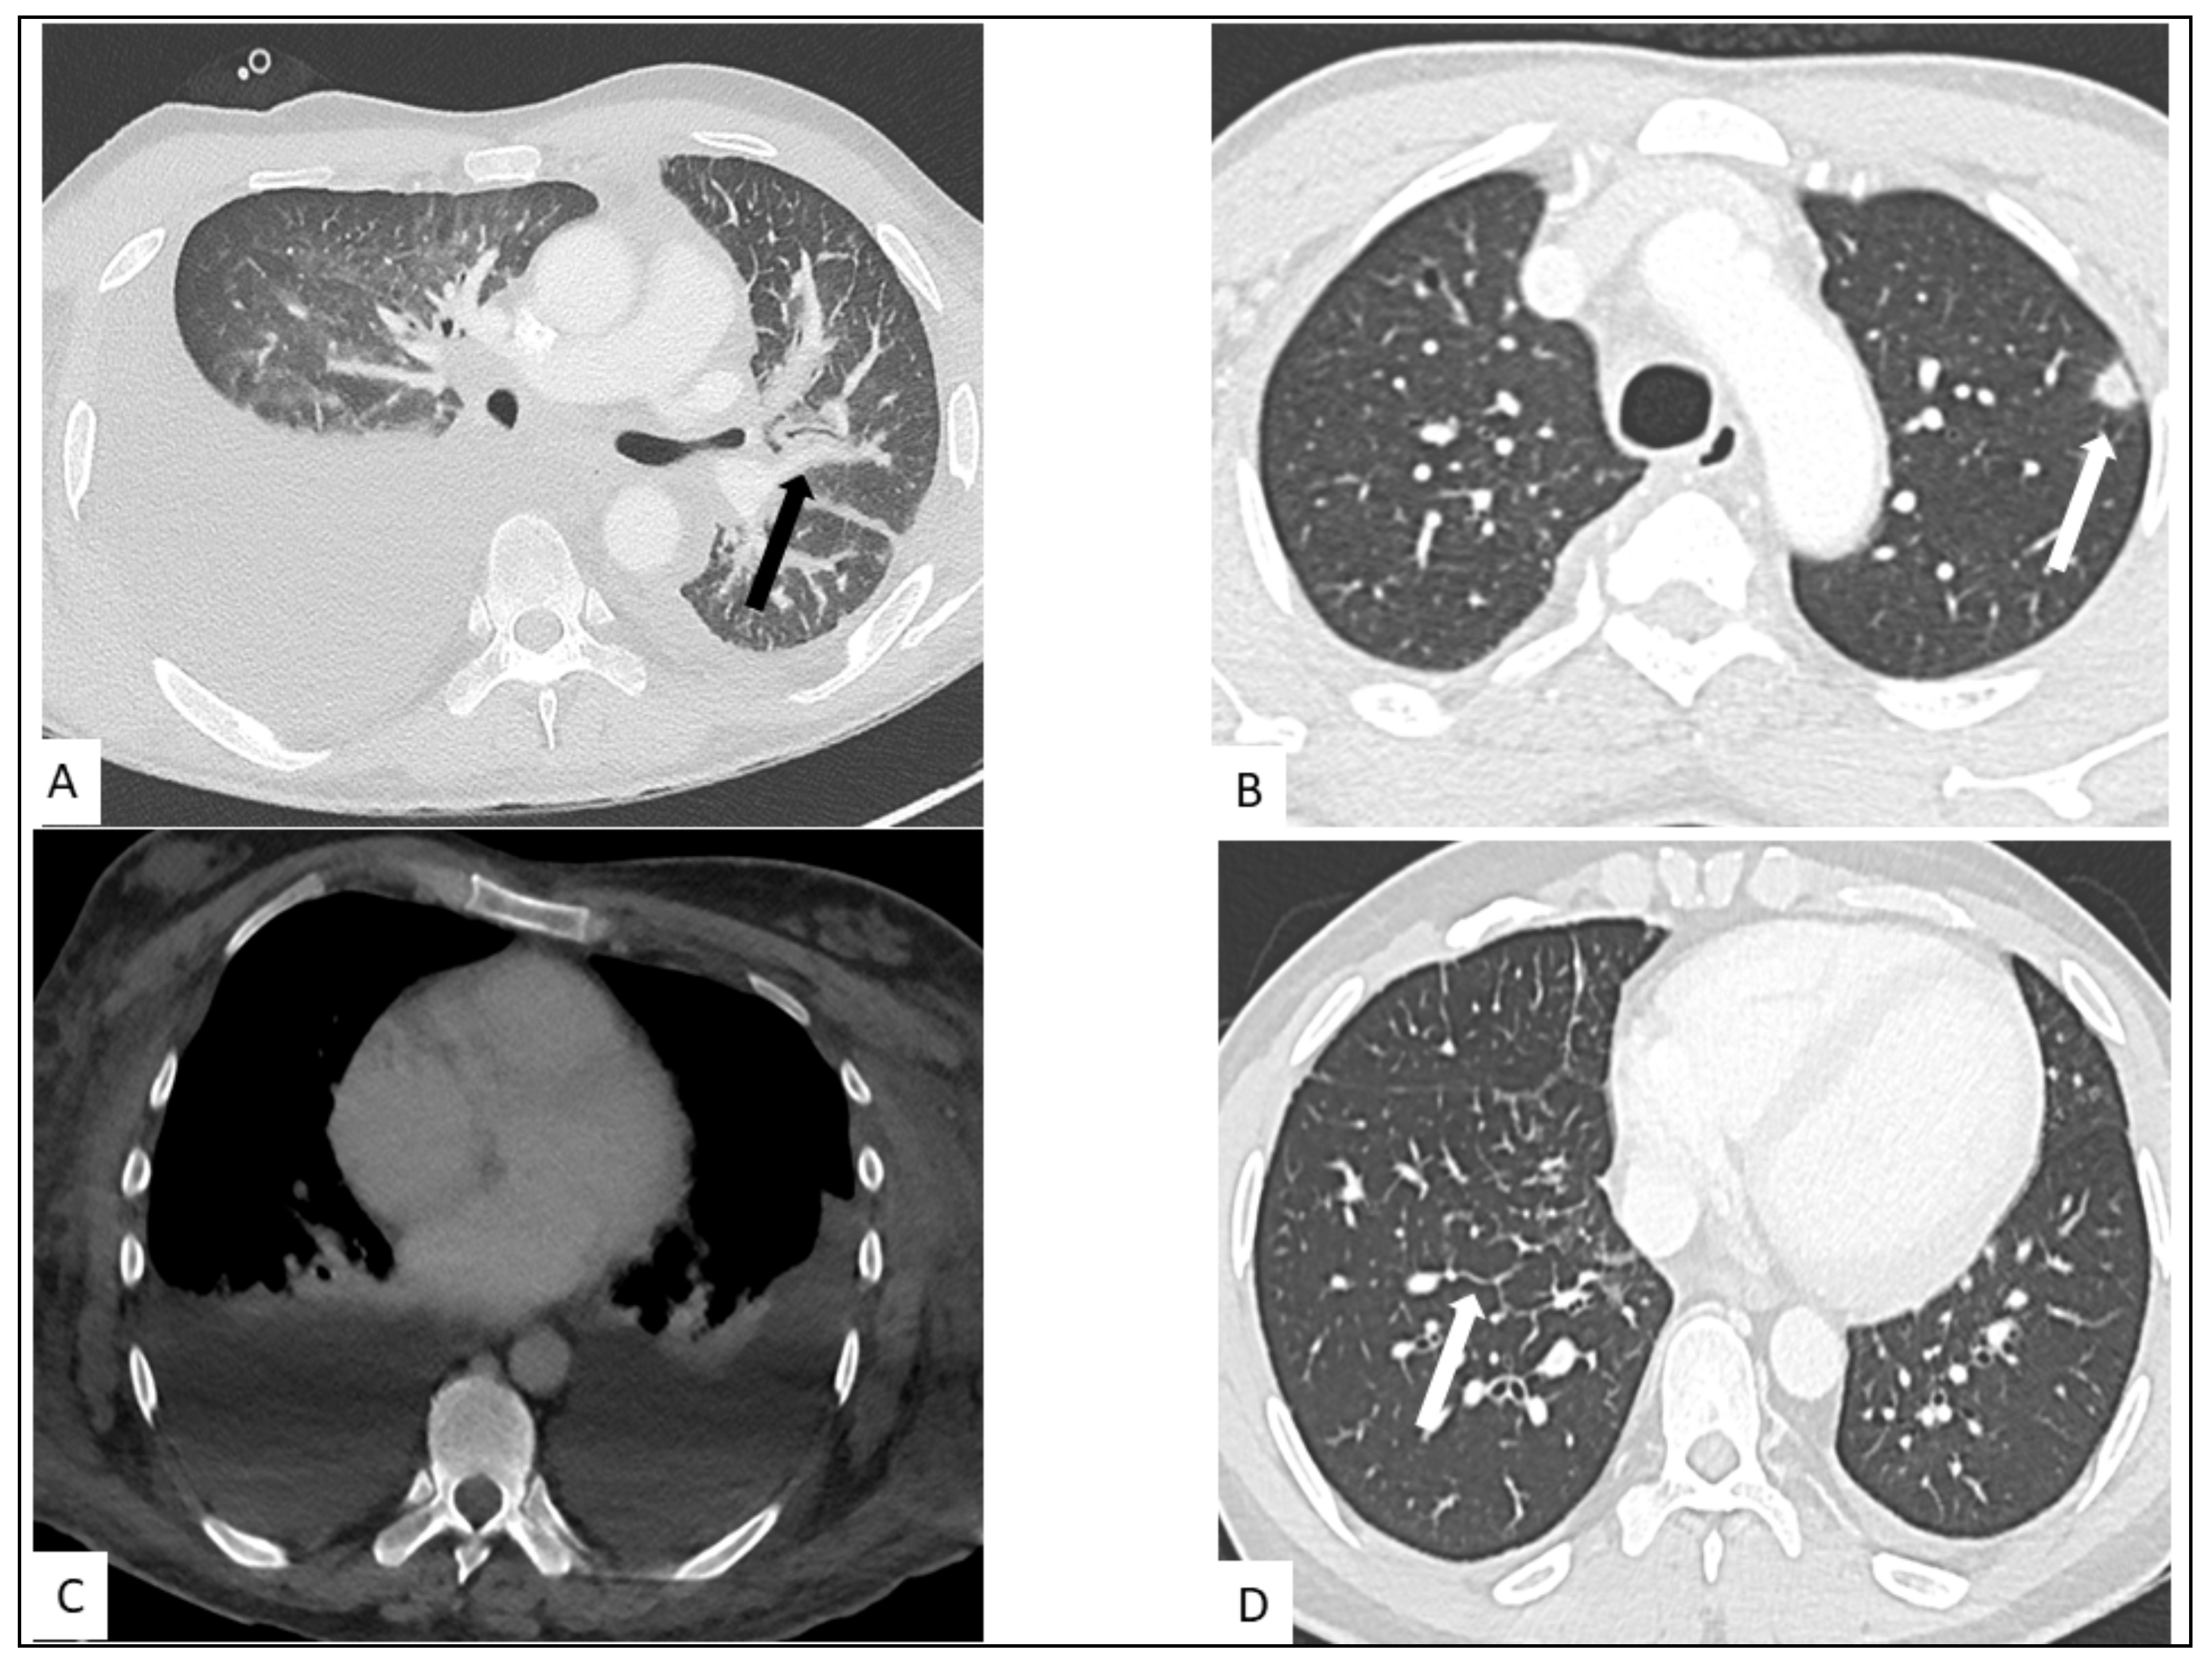

5.1. Pulmonary KS

- Restrepo, C.S.; Martínez, S.; Lemos, J.A.; Carrillo, J.A.; Lemos, D.F.; Ojeda, P.; Koshy, P. Imaging Manifestations of Kaposi Sarcoma. Radiographics 2006, 26, 1169–1185. [Google Scholar] [CrossRef]

- Traill, Z.C.; Miller, R.F.; Shaw, P.J. CT Appearances of Intrathoracic Kaposi’s Sarcoma in Patients with AIDS. Br. J. Radiol. 1996, 69, 1104–1107. [Google Scholar] [CrossRef]

- Khalil, A.M.; Carette, M.F.; Cadranel, J.L.; Mayaud, C.M.; Bigot, J.M. Intrathoracic Kaposi’s Sarcoma. CT Findings. Chest 1995, 108, 1622–1626. [Google Scholar] [CrossRef]

- Gasparetto, T.D.; Marchiori, E.; Lourenço, S.; Zanetti, G.; Vianna, A.D.; Santos, A.A.S.M.D.; Nobre, L.F. Pulmonary Involvement in Kaposi Sarcoma: Correlation between Imaging and Pathology. Orphanet J. Rare Dis. 2009, 4, 18. [Google Scholar] [CrossRef]

- Javadi, S.; Menias, C.O.; Karbasian, N.; Shaaban, A.; Shah, K.; Osman, A.; Jensen, C.T.; Lubner, M.G.; Gaballah, A.H.; Elsayes, K.M. HIV-Related Malignancies and Mimics: Imaging Findings and Management. Radiographics 2018, 38, 2051–2068. [Google Scholar] [CrossRef]

- Da Silva Filho, F.P.; Marchiori, E.; Valiante, P.M.; Escuissato, D.L.; Gasparetto, T.D. AIDS-Related Kaposi Sarcoma of the Lung Presenting with a "Crazy-Paving" Pattern on High-Resolution CT: Imaging and Pathologic Findings. J. Thorac. Imaging 2008, 23, 135–137. [Google Scholar] [CrossRef]

- Allen, C.M.; Al-Jahdali, H.H.; Irion, K.L.; Al Ghanem, S.; Gouda, A.; Khan, A.N. Imaging Lung Manifestations of HIV/AIDS. Ann. Thorac. Med. 2010, 5, 201–216. [Google Scholar] [CrossRef]

- Gouny, P.; Lancelin, C.; Girard, P.M.; Hocquet-Cheynel, C.; Rozenbaum, W.; Nussaume, O. Pericardial Effusion and AIDS: Benefits of Surgical Drainage. Eur. J. Cardio-Thorac. Surg. Off. J. Eur. Assoc. Cardio-Thorac. Surg. 1998, 13, 165–169. [Google Scholar] [CrossRef][Green Version]

- Hussenet, C.; Calin, R.; Boussouar, S.; Londner, C.; Caby, F.; Tubiana, R.; Pourcher, V. Chylothorax as a complication of Kaposi’s sarcoma in an AIDS patient. Med. Mal. Infect. 2018, 48, 66–69. [Google Scholar] [CrossRef]

- Lababidi, M.H.; Alhawasli, H.; Iroegbu, N. Kaposi Sarcoma Can Also Involve the Heart. J. Community Hosp. Intern. Med. Perspect. 2015, 5, 29054. [Google Scholar] [CrossRef]